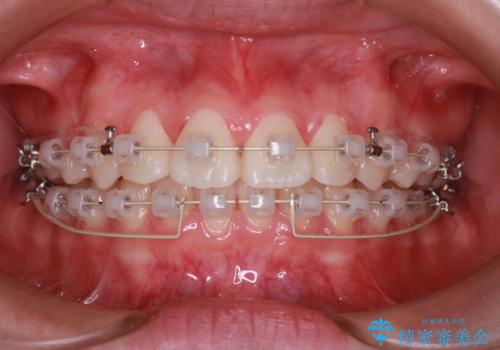

- 患者様は、全体的な歯列のガタガタとディープバイト(深い噛み合わせ)を主訴として来院されました。診断の結果、ディープバイトを改善するためには、歯列全体の拡大が必要であると判断しました。治療には、透明なマウスピース型矯正装置「インビザライン」を使用し、歯を適切に拡大しながら歯並びを整える計画を立てました。治療期間はおおよそ2年を見込んで進め、最終的に見た目にも大きく変化をもたらすことを目指しました。

ディープバイトの治療には、奥歯の高さや前歯の位置に対する繊細な調整が必要です。本症例では、インビザラインによる歯列拡大を行うことで、噛み合わせを改善し、歯並び全体を整えました。治療過程では、歯間のスペースを確保するため、IPR(インタープロキシマルリダクション)を適宜行い、無理なく歯列の調整を行いました。治療後は、歯並びが大きく改善され、患者様の見た目にも大きな変化が現れました。インビザラインは透明で目立たず、治療中の見た目を気にされる患者様にも配慮した治療法です。